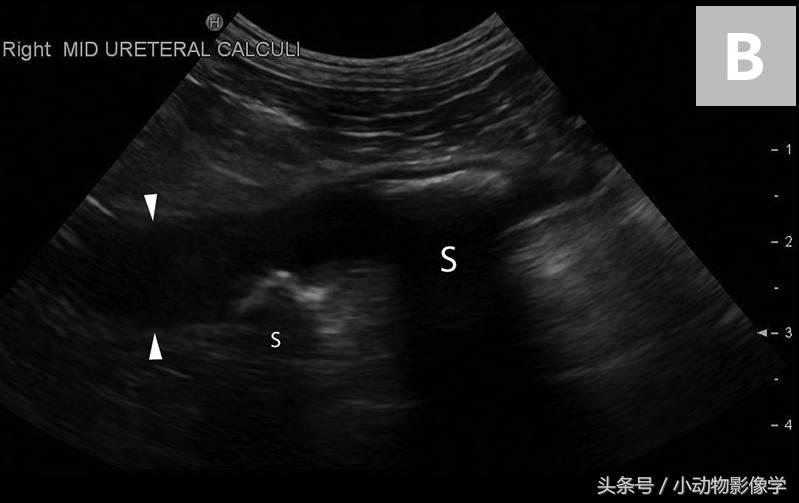

图6A、一只大麦町犬轻度至中度的右肾盂积水和近端输尿管扩张。

图6B、这是导致图6A中犬尿道梗阻和肾盂积水的右侧输尿管结石(准星之间)的超声图像。注意输尿管结石附近的输尿管扩张(三角箭头之间)。